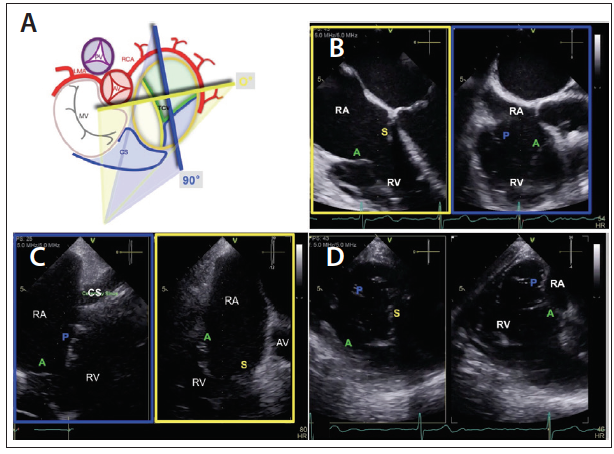

TEE examination of the tricuspid valve usually starts at the midesophageal depth. In this view, the septal and the anterior leaflets are imaged, and when a simultaneous biplane imaging is used, the posterior leaflet can be visualized (Figure 4A and 4B). Inserting the probe further into the distal esophagus will facilitate excluding the left-sided structure. At the distal esophageal level, the coronary sinus is visualized and the leaflets that are usually visualized are the anterior and posterior leaflets (Figure 4C). The other important TEE window is the transgastric view because simultaneous biplane imaging allows tricuspid valve enface visualization in which the three leaflets are imaged (Figure 4D).

Figure 4. Panel A represents schematic of the TV as viewed from the RA and the correlating TEE midesophageal biplane windows. Panel B shows the midesophageal biplane view of the tricuspid valve at 0° (yellow box) and at 90° (blue box). Panel C represents the deep-esophageal view of the TV in which the posterior and anterior leaflets are visualized; note the absence of left-sided structures in this view. Panel D displays the transgastric biplane view of the TV at 0° and 90° (in this patient with severe TR and dilated RV, the heart is slightly rotated and what is visualized at 0° is usually seen at higher angles). The transgastric view allows imaging the TV en face to simultaneously display the three leaflets (P in the near field, A in the far field, and S on the right side). A, anterior leaflet; AV, aortic valve; CS, coronary sinus; LMA, left main artery; MV, mitral valve; P, posterior leaflet; RA, right atrium; RCA, right coronary artery; RV, right ventricle; S, septal leaflet; TEE, transesophageal echocardiography; TV, tricuspid valve.